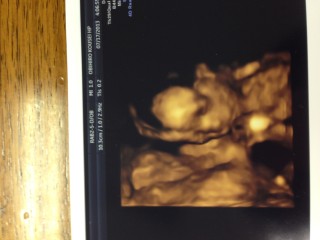

感動した一枚、4dエコーする前に 他の人の4d写真見漁ってたから 参考になればと思い投稿してみます。